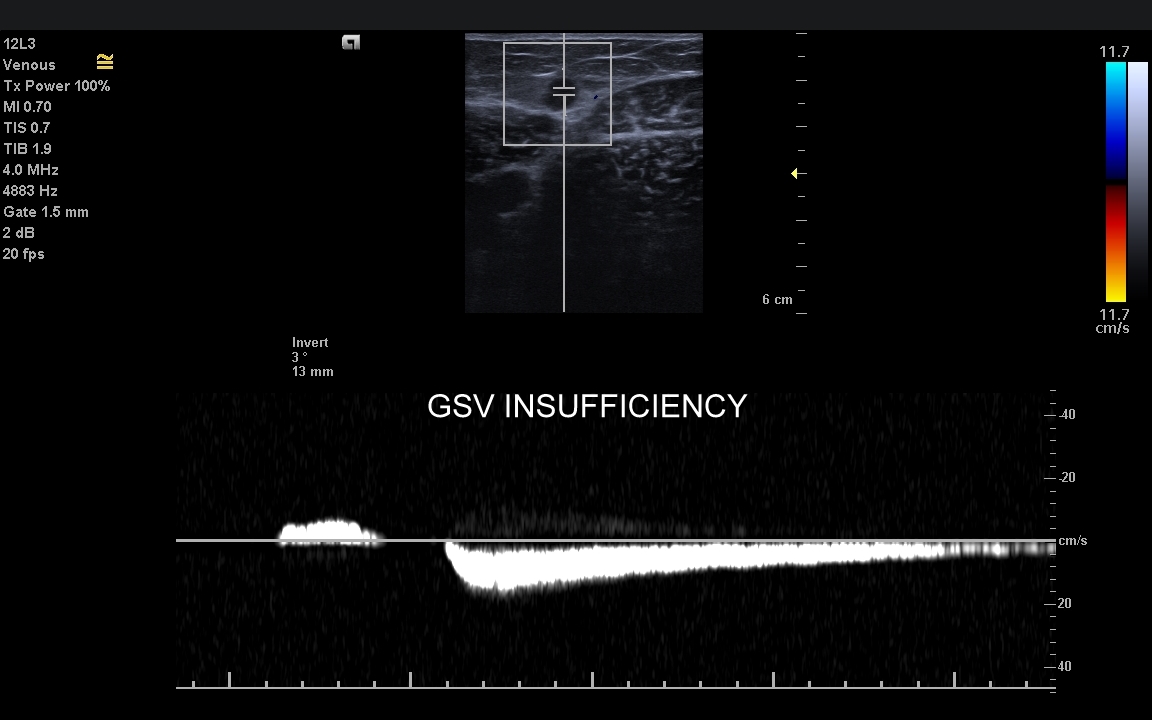

Żyły kończyn dolnych. W obrębie żył kończyn dolnych znajdują się dwa zasadnicze układy żylne – układ żył głębokich i układ żył powierzchownych. Oba układy łączą się razem bezpośrednio w okolicy pachwiny oraz dołu podkolanowego; poza tym na różnych poziomach kończyny przy pomocy żył przeszywających. Każde połączenie układu głębokiego i powierzchownego posiada naturalnie zastawkę, która zapobiega cofaniu się krwi w niewłaściwym kierunku. Prawidłowym kierunkiem jest przepływ z układu powierzchownego do głębokiego oraz ku sercu. Zarówno w układzie powierzchownym, jak i głębokim lokalizować mogą się poważne choroby takie jak zakrzepica, czy niewydolność żylna.

Czym są żylaki? Żylaki to nadmierne i niefizjologiczne poszerzenie odcinka żyły pod wpływem podwyższonego ciśnienia żylnego i zastoju krwi. W poszerzonej żyle dochodzi do zaburzenia, spowolnienia, a nawet odwrócenia kierunku przepływu krwi. Czynniki te sprzyjają wystąpieniu zakrzepicy, a także rozwoju niekorzystnych zmian w strukturze skóry i tkanki podskórnej, które zakończyć się mogą owrzodzeniem kończyny. Zdiagnozowanie przyczyny i źródła żylaków umożliwia zastosowanie celowanego zabiegu chirurgicznego

Badanie USG żył kończyn dolnych najczęściej wykonywane jest w ramach diagnostyki niewydolności żył powierzchownych oraz ich objawów w postaci pajączków żylnych, żylaków kończyn dolnych, obrzęków i owrzodzeń żylnych. Kolejnym pod względem częstości wskazaniem do badania Doppler żył jest podejrzenie zakrzepicy żył głębokich kończyn dolnych, monitorowanie leczenia zakrzepicy oraz ocena jej powikłań odległych. Powikłaniem nieleczonej zakrzepicy żył głębokich może być zespół pozakrzepowy manifestujący się masywnymi obrzękami kończyny i zaburzeniami troficznymi. Badanie USG Doppler żył kończyn dolnych często uzupełniane jest oceną układu żył centralnych w miednicy i jamie brzusznej. W tych obszarach również pojawiać się mogą żylne zmiany zakrzepowe, niedrożności żył, a nawet zmiany nowotworowe.

Podczas najczęściej przeprowadzanego badania, tj. USG Doppler kończyn dolnych, oceniane są żyły głębokie oraz powierzchowne na całej długości kończyny – od stóp aż do pachwiny. Czasami mogą zaistnieć wskazania do rozszerzenia badania na wyższy poziom układu żylnego, tj. na żyły biodrowe w miednicy i żyłę główną dolną w jamie brzusznej. Badanie USG żył jest badaniem dynamicznym, tzn. oprócz oceny wyglądu żył wykonuje się różnorodne próby czynnościowe, takie jak kompresja, głębokie oddychanie, próba Valsavy, podczas których rejestruje się przepływy krwi w żyłach.

W przypadku oceny wydolności żył oraz kwalifikacji Pacjenta do zabiegu na żyłach lub na żylakach kończyn dolnych dynamiczne badanie dopplerowskie żył wykonuje się także w pozycji pionowej. Przy opisanych próbach czynnościowych wykorzystuje się specjalne właściwości sprzętu USG, tj. tryby badań dopplerowskich, tryby duplex i triplex, a także angografię sonograficzną dostępną w aparatach wysokiej klasy.

Czy USG Doppler wykrywa przyczynę żylaków? Zdecydowanie tak. Przyczyną żylaków kończyn dolnych najczęściej jest niewydolność żył powierzchownych na poziomie uda, ale żylaki wynikać mogą także z istnienia krążenia obocznego powstałego na tle niedrożności żył głębokich lub rzadkich malformacji naczyniowych. Uwaga! Przed leczeniem żylaków zawsze należy wykonać szczegółowe badanie USG Doppler!